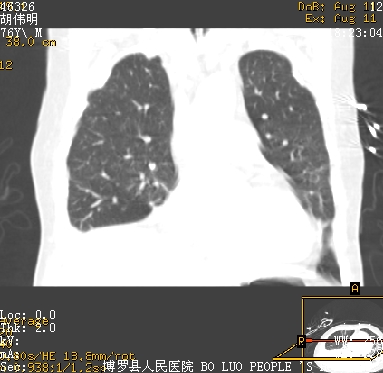

icu病人,几天都没明确诊断。m,76y,咳嗽、咳痰1周,伴气促,右胸痛入院,pe:t38.3c p135 r25 bp135/85。双肺可闻及大量湿罗音,心、腹未见明显异常。诊断:1心衰?2肺部感染?3冠心病?

11号ct

大叶性肺炎、胸腔积液

双肺感染性病变,下叶膨胀不全,胸水,左室大。

1)两肺感染性病变(右肺下叶肺脓肿可能)。2)双侧胸腔积液,以右侧为甚。

考虑双肺感染、右肺下叶肺脓肿伴双侧胸腔积液。

ards,肺感染性病变,右下叶实变,双侧胸腔积液,右侧为著,叶间胸膜积液,右上肺陈旧性tb纤维灶,左室大。